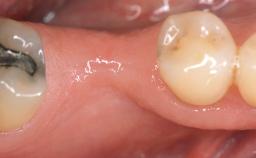

GBR and Soft-Tissue Augmentation Following Explantation to Rehabilitate a Soft- and Hard-Tissue Defect

It is sometimes necessary to remove and replace compromised implants. This case is a clear example of the need for multiple steps to achieve an optimal therapeutic result for patients with non-salvageable implants. It illustrates how the lost soft and hard tissues were rebuilt in a sequence that improved the healing of the hard tissues and assured their long-term stability. The 35-year-old healthy patient presented with clinical attachment loss on the proximal and lingual surfaces of the natural dentition. Some gingival recession was present on natural teeth, particularly in the posterior sextants (S1, S3, S4, and S6).

Bone Augmentation Horizontal|Staged|Vertical

Augmentation Materials Autogenous chips|Autogenous block(s)|Xenogenous